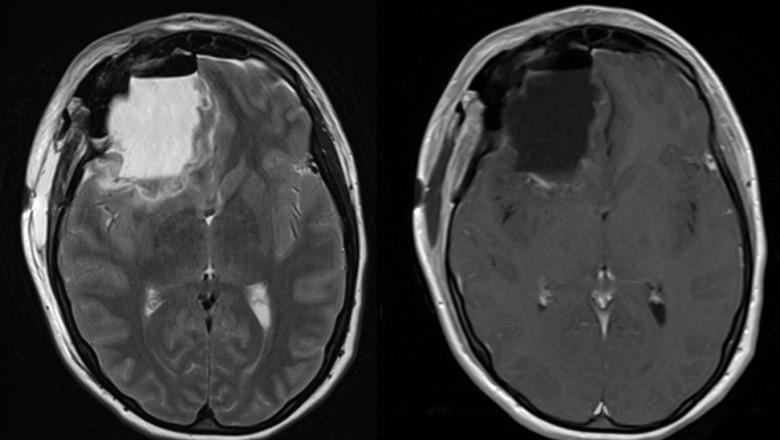

Peste 100 de persoane care au absolvit același liceu din New Jersey au fost diagnosticate cu forme rare de cancer cerebral, context în care a fost declanșată o investigație pentru a se stabili dacă există vreo legătură între ele.

Investigația demarată luna trecută a vizat contextul în care peste 100 de elevi care au mers la același liceu din New Jersey au făcut o formă rară de cancer cerebral. Ancheta nu a găsit nicio legătură între școală și diagnostic.

Luna trecută, Al Lupiano a spus că a fost diagnosticat cu această boală când avea 27 de ani. Ulterior, sora și soția lui au fost și ele diagnosticate cu cancer cerebral. Toți trei au urmat cursurile liceului Colonia din Woodbridge, New Jersey, scrie Insider.

NBC Today a raportat că peste 100 de elevi care au mers la acel liceu au avut același diagnostic.